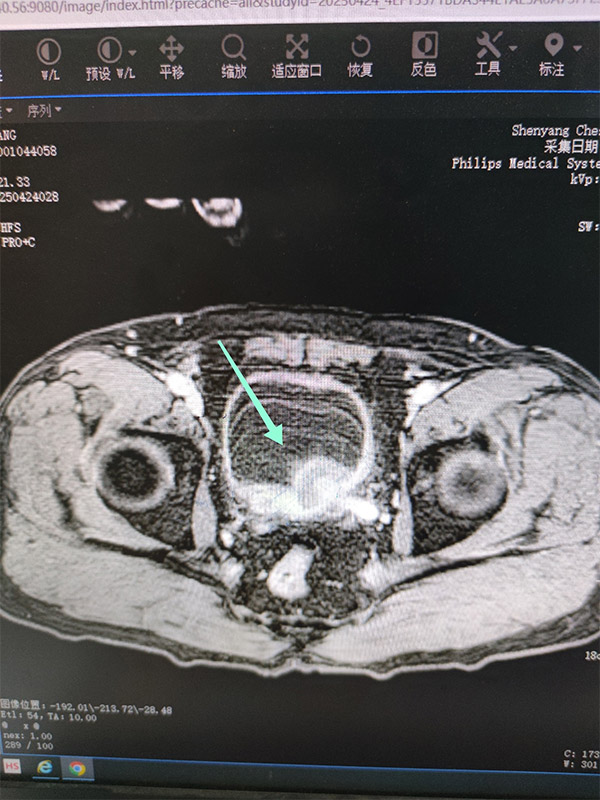

马先生经历了全腹CT、PSA及前列腺MR增强等检查—可疑膀胱癌与前列腺癌的阴影笼罩在他的心头。

前列腺穿刺活检术与膀胱镜活检如同精准的狙击手,直击病灶,膀胱镜下,前列腺有较多边界不清的灰白色结节与正常前列腺组织对比明显,突出于前列腺平面,正常前列腺腺体结构消失,以及膀胱三角区的大范围广基地的多发菜花样肿瘤,无一不在诉说着疾病的狰狞。

病理结果的出炉,如同晴天霹雳——膀胱高级别浸润性尿路上皮癌与前列腺腺癌,双原发恶性肿瘤的残酷现实摆在了马先生及其家属的面前,并且膀胱癌已侵及前列腺,但尚未出现更远处转移。